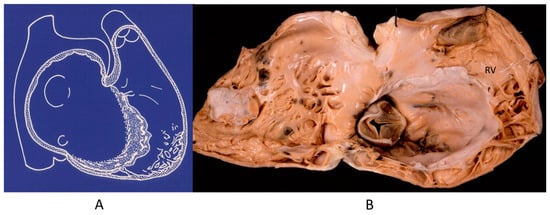

Also, progressive AV block (Figure 21), usually manifesting in in elderly patients, may be genetically determined due to a mutation of the SN5 (Sodium channel five) gene.

Figure 21.

Electrocardiogram with AV block (A). At histology, bifurcation of His bundle with fibrous interruption of the left bundle branch (B) and the right bundle branch (C) were observed [15].